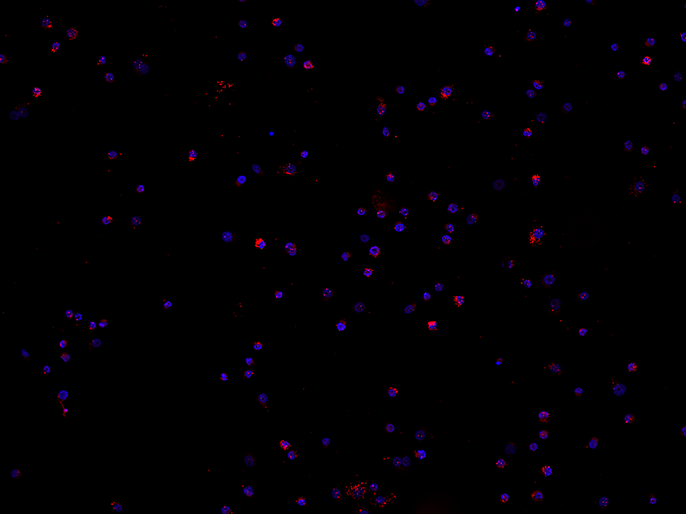

3. Drug Development: Neddylation-Inhibitor

Zurzeit wird in klinischen Studien ein Neddylation-Inhibitor getestet, dessen Wirkung noch nicht vollständig erforscht ist. Wie sich das neue Medikament auf hämatopoetische Vorläuferzellen und deren Differenzierung auswirkt, wird auch von der AG Gattermann untersucht. Unter anderem wird mit dem Proximity Ligation Assays (PLA) am Epidermal Growth Factor Receptor (EGFR) die Homodimerisierung des Rezeptors an der Zelloberfläche nachgewiesen, die eine Rezeptor-Phosphorylierung im Zellinneren nach sich zieht und somit Signalwirkung im Hinblick auf Zellproliferation entfaltet. Zum Zeitpunkt des Interviews mit Professor Gattermann konnten noch keine genaueren Angaben gemacht werden, weil sich erste Ergebnisse noch im Veröffentlichungsprozess befinden.